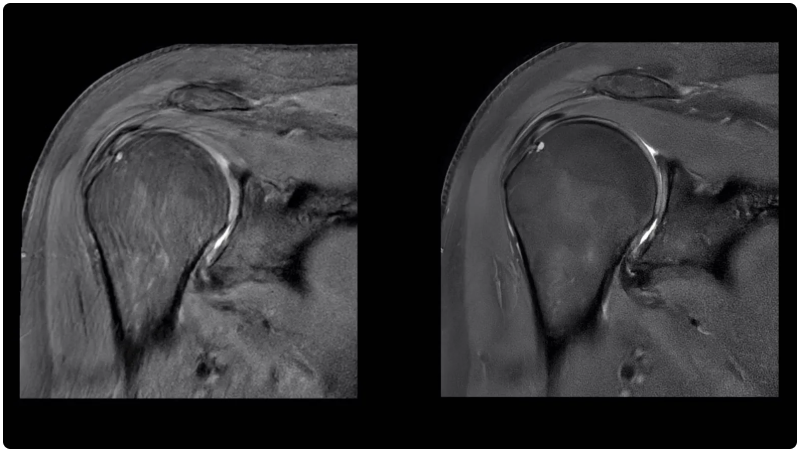

肩部掃描圖像(左)與使用人工智能功能銳化后的相同圖像(右)進(jìn)行對(duì)比。Air Recon DL 是通用電氣醫(yī)療集團(tuán)的旗艦人工智能產(chǎn)品之一,旨在提高圖像質(zhì)量,縮短核磁共振成像掃描時(shí)間。

自2022年MedTech Dive首次分析FDA數(shù)據(jù)以來,通用電氣醫(yī)療集團(tuán)(GE Healthcare)和西門子醫(yī)療集團(tuán)(Siemens Healthineers)的人工智能設(shè)備數(shù)量位居榜首。截至2024年8月7日,通用電氣醫(yī)療集團(tuán)共有81臺(tái)人工智能設(shè)備獲得授權(quán)。其旗艦人工智能產(chǎn)品之一 Air Recon DL 于 2020 年推出。通用電氣醫(yī)療保健公司的人工智能宣傳負(fù)責(zé)人Jan Beger說,這種算法可以提高圖像質(zhì)量,并將核磁共振掃描時(shí)間最多縮短50%。截至 2024 年 10 月,該公司已使用該軟件掃描了 3400 多萬名患者。Beger 將通用電氣醫(yī)療保健公司的人工智能方法分為三類:用于提高成像效率的 Air Recon DL 等產(chǎn)品、從各種來源提取數(shù)據(jù)以幫助臨床醫(yī)生做出決策的人工智能以及用于規(guī)劃的企業(yè)級(jí)系統(tǒng)。有時(shí),這些功能內(nèi)置在公司銷售的成像設(shè)備中。在其他情況下,通用電氣醫(yī)療保健公司會(huì)將這些功能作為單獨(dú)的訂購(gòu)產(chǎn)品出售。“總的來說,人工智能的理念其實(shí)是,我們?nèi)绾尾拍軐⑷哂?、重?fù)、平凡的任務(wù)自動(dòng)化?”Beger說。